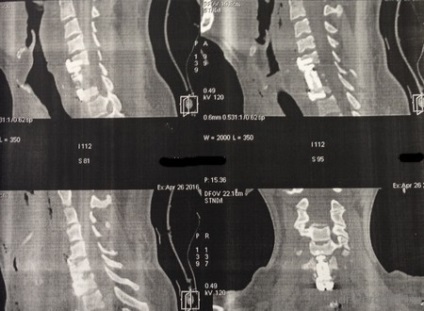

După un curs de detoxifiere și terapia masivă cu antibiotice pacientul a fost pregătit pentru o intervenție chirurgicală. Sa decis să efectueze îndepărtarea corpurilor vertebrale L1 L2 și discul între ele, iar placa corporodesis Masham umplut de os proprii (în acest caz, o margine) în China. Cel mai adesea, atunci când aveți nevoie pentru a manipula 1 vertebre vom trata accesul antero lateral deasupra sau dedesubtul diafragmei. În această situație, operarea cu cotorul de tranziție care implica doua fuziune vertebre apare între TN12 și L3, în total 4 trebuie să expună o vertebră și, prin urmare, a trebuit să folosească TORAKOFRENOLYUMBOTOMIYU. Accesul de-a lungul marginii cu deschiderea cavității pleurale și disectia retroperitoneale și diafragmei pe dreptul său semiperimetrul.

stadiu vizibil de funcționare după instalarea plasei între corpurile vertebrale. Operarea peste toracostomie placa spondylosyndesis (care a fost distrusă după ce a suferit purulent pleurita).

La filmele de control după implanturi chirurgie bună stare, decompresie este realizată în mod adecvat.